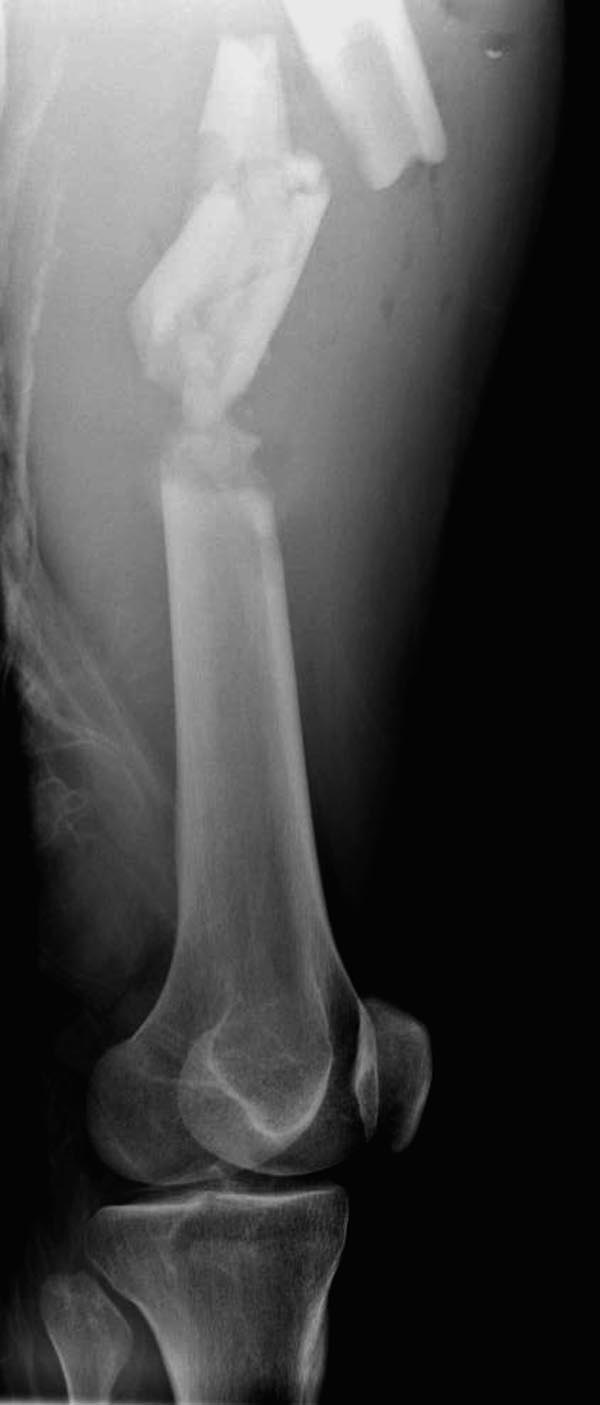

Здесь выставлен ренгенограммы больного, ему 21, травму получил в

результате высокоскоростной погони на украденной машине, которая

закончилась смертью трех остальных“боевых комрадов”. Начатую коллегой

открытую операцию на шейке пришлось закончить мне, установкой винтов и

ретроградной фиксацией бедра. Выписка в обычное сроки и наблюдался

амбулаторно. Каждый раз напоминали о возможности осложнений ввиде

несращения! По истечению 4 месяцев появились признаки варусной

деформации. На СТ срезах несращение шейки и бедра. Риминг, замена на

более толстый гвоздь и вальгусная остеотомия.